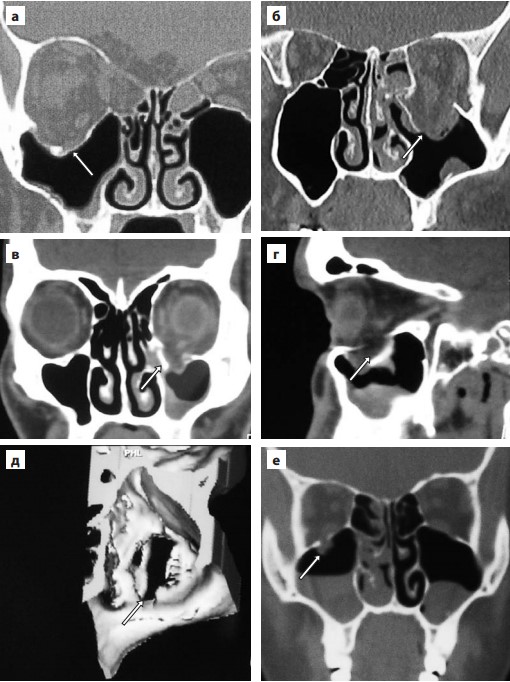

Показания к операции

а — тотальный перелом,

б — существенное увеличение объема,

в — дефект н. стенки, равный 0,5 ее S в корональной проекции,

г — дефект н. стенки, равный 0,5 ее S в сагиттальной проекции,

д — трехмерная реконструкция.

е — ущемление н. прямой м. в зоне линейного «перелома-капкана».